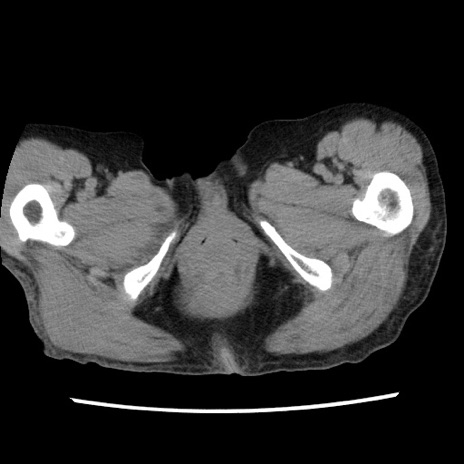

症例1(横断像)

【症例】80歳代女性

【主訴】腹痛

【現病歴】8時間前から腹痛あり来院。

【既往歴】糖尿病、脂質異常症、子宮体癌にて子宮全摘術

【身体所見】意識清明・会話良好だが腹痛で苦悶様、全腹部にわたって反跳痛と圧痛あり

【データ】WBC 13600、CRP 0.14、LDH 224、CK 90